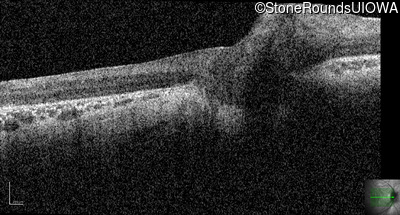

Optical Coherence Tomography - Right - 10/300 sc

Exemplar / OCT Stack